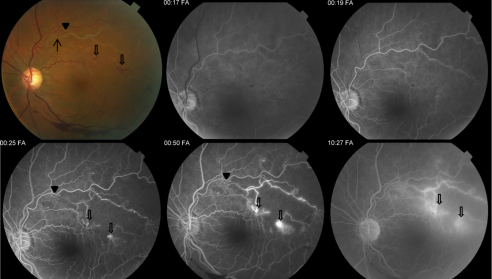

Typical funduscopic examination consists of flame hemorrhages, dot-and-blot hemorrhages, cotton-wool spots, hard exudates, retinal edema, and dilated tortuous veins (Figure 1). Classically there is a wedge-shaped distribution of intraretinal hemorrhage that is more extensive if the occlusion is ischemic compared to a nonischemic BRVO. A hemorrhage can be present at the arteriovenous crossing, which is called the Bonnet sign.[29] The Bonnet sign in hypertensive retinopathy denotes banking (dilatation) of the vein distal to the arteriovenous crossing.

In patients with chronic BRVO, the intraretinal hemorrhages are absorbed and subsequent retinal vascular abnormalities develop in the distribution of the BRVO. The resulting changes include capillary nonperfusion, collateral formation, microaneurysms, sclerosed veins, and telangiectatic vessels (Figure 2).

The characteristic FA for BRVO shows delayed filling of the occluded retinal vein with varying degrees of capillary nonperfusion. Intraretinal hemorrhages will result in blockage, and macular edema or retinal neovascularization will result in dye extravasation (Figure 3).